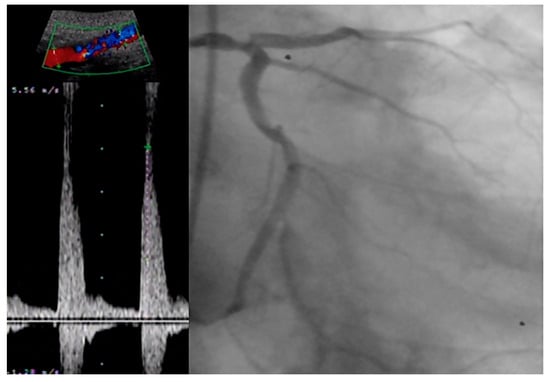

- Tătaru, D.A.; Olinic, M.; Homorodean, C.; Ober, M.C.; Spînu, M.; Lazăr, F.L.; Onea, L.; Olinic, D.M. Correlation between Ultrasound Peak Systolic Velocity and Angiography for Grading Internal Carotid Artery Stenosis. J. Clin. Med. 2024, 13, 517. [Google Scholar] [CrossRef] [PubMed]

- Artyszuk, Ł.; Błażejowska, E.; Danielecka, Z.; Jurek, J.; Olek, E.; Abramczyk, P. Peripheral atherosclerosis evaluation through ultrasound: A promising diagnostic tool for coronary artery disease. Echocardiography 2023, 40, 841–851. [Google Scholar] [CrossRef]

- Achim, A.; Kákonyi, K.; Nagy, F.; Jambrik, Z.; Varga, A.; Nemes, A.; Chan, J.S.K.; Toth, G.G.; Ruzsa, Z. Radial Artery Calcification in Predicting Coronary Calcification and Atherosclerosis Burden. Cardiol Res Pract. 2022, 2022, 5108389. [Google Scholar] [CrossRef]